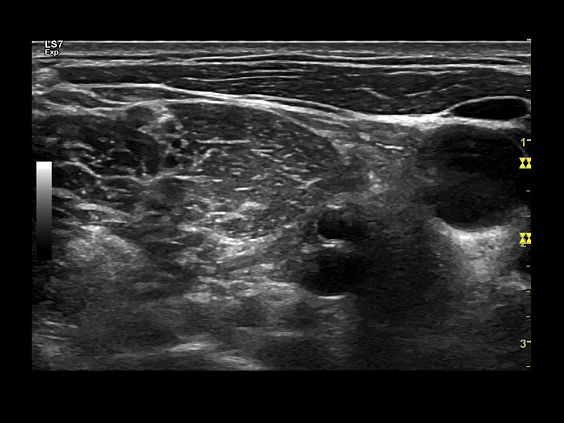

Клинические изображения

Logiq S7 XDclear — УЗИ аппарат нового поколения, который обеспечивает простой и комфортный рабочий процесс, высокую производительность и предлагает широкий набор современных инструментов для проведения уверенной диагностики. Его расширенный функционал включает такие возможности как B-Flow — недопплеровская технология отображения кровотока в B-режиме, компрессионная эластография (качественная и полуколичественная), количественный анализ васкуляризации, функцию В-Steer+ — изменение угла наклона УЗ луча в B-режиме, 3D/4D диагностику и мультимодальную визуализацию.

Ультразвуковой аппарат LOGIQ S7 XDclear предназначен для использования специалистами из различных областей диагностики. Его расширенный функционал включает такие возможности как B-Flow — недопплеровская технология отображения кровотока в B-режиме, компрессионная эластография (качественная и полуколичественная), количественный анализ васкуляризации, функцию В-Steer+ — изменение угла наклона УЗ луча в B-режиме, 3D/4D диагностику и мультимодальную визуализацию.